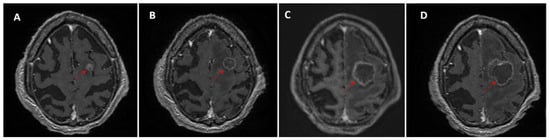

Temporal Dynamics and Heterogeneity in Brain Metastases: A Single-Center Retrospective Analysis of Vulnerabilities in Current MRI Surveillance Practices

by Claudia Tocilă-Mătășel, Sorin Marian Dudea and Gheorghe Iana

Medicina 2026, 62(1), 187; https://doi.org/10.3390/medicina62010187 (registering DOI) - 16 Jan 2026

Background and Objectives: Brain metastases frequently evolve over time in multiple waves, especially in patients with prolonged survival. Despite repeated imaging and targeted therapies, lesion-level continuity is fragmented in clinical practice, as follow-up is typically limited to pairwise MRI comparisons. The aim of the study is to assess the ability of routine narrative MRI follow-up reports to preserve longitudinal lesion identity and to reconstruct a coherent trajectory of disease evolution. Materials and Methods: We conducted a single-center, retrospective, observational study of all brain MRI examinations performed between June 2024 and June 2025 (n = 731 scans, 616 patients). All imaging reviews and longitudinal lesion tracking were performed by one board-certified neuroradiologist. Adult patients with confirmed brain metastases and at least three MRI examinations (including external studies) were included. We assessed the concordance of routine narrative MRI follow-up reports against a longitudinal review of all available MRIs and treatment timelines, which served as the reference standard. Lesion identity was considered preserved when reports explicitly recognized and linked lesions across time points, and lost when identity was omitted or ambiguous in at least one report. Results: The final cohort comprised 73 patients (477 tracked lesions). More than half of monitored lesions disappeared (42.9%) or evolved into post-treatment sequelae (9.9%), and were omitted from narrative reports, limiting retrospective recognition without prior imaging. The ability of routine reports to preserve lesion identity declined as cases became more complex. Concordance was higher in uniform evolution patterns (≈60%) but dropped to 18.2% in mixed evolution. A similar decline was seen with sequential metastatic waves, defined as new metastases appearing at distinct time points: 65.2% (1 wave), 46.7% (2 waves), 18.2% (3 waves), and complete loss of continuity when >3 waves occurred. Conclusions: Routine narrative MRI follow-up reports generally provide adequate information in simple cases with uniform lesion behavior, but tend to lose critical details as disease trajectories become more complex, particularly in heterogeneous or multi-wave disease. Even when individual lesions are identified across examinations, documentation remains fragmented and reflects only a snapshot of the disease course rather than an integrated longitudinal perspective. These findings highlight a critical vulnerability in current follow-up practices. Improving lesion-level continuity, potentially through AI-assisted tools, may enhance the accuracy, consistency, and clinical utility of MRI surveillance in patients with brain metastases. Full article

Figure 1